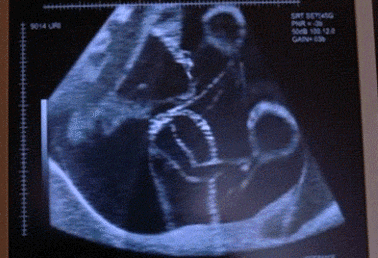

宝宝不老实,胎动力度大,尤其是孕晚期宝宝处于头位,头朝下,脚朝上。胎动时宝宝可能会踢到妈妈的肋骨,而且与怀孕早期中期相比,胎动力度更大,引起肋骨疼痛。